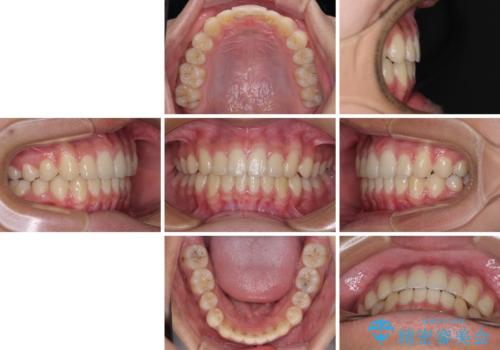

突き上げによる隙間を予防する為に、深い咬み合わせを改善するような治療計画としました。咬み合わせを改善させることはできましたが、隙間は後戻りしやすいので、通常の下顎前歯のみではなく、上顎前歯2本もワイヤーで保定を行いました。

高校生ということで、非常に短期間で治療を終えることができました。